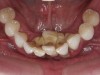

The main biological consideration with cement-retained implant restorations is the vulnerability of peri-implant tissues. Cement contamination readily occurs around implant sites for many reasons. First, as previously mentioned, the soft tissues are much more delicate and vulnerable to tearing when using protection techniques such as retraction cord placement, which is, therefore, contraindicated.16 Cord placement has been shown to strip the weak hemidesmosomal attachment and provide a pathway along the side of the implant for cement extrusion to occur (Figure 1 and Figure 2).17

Figure 1

Figure 2